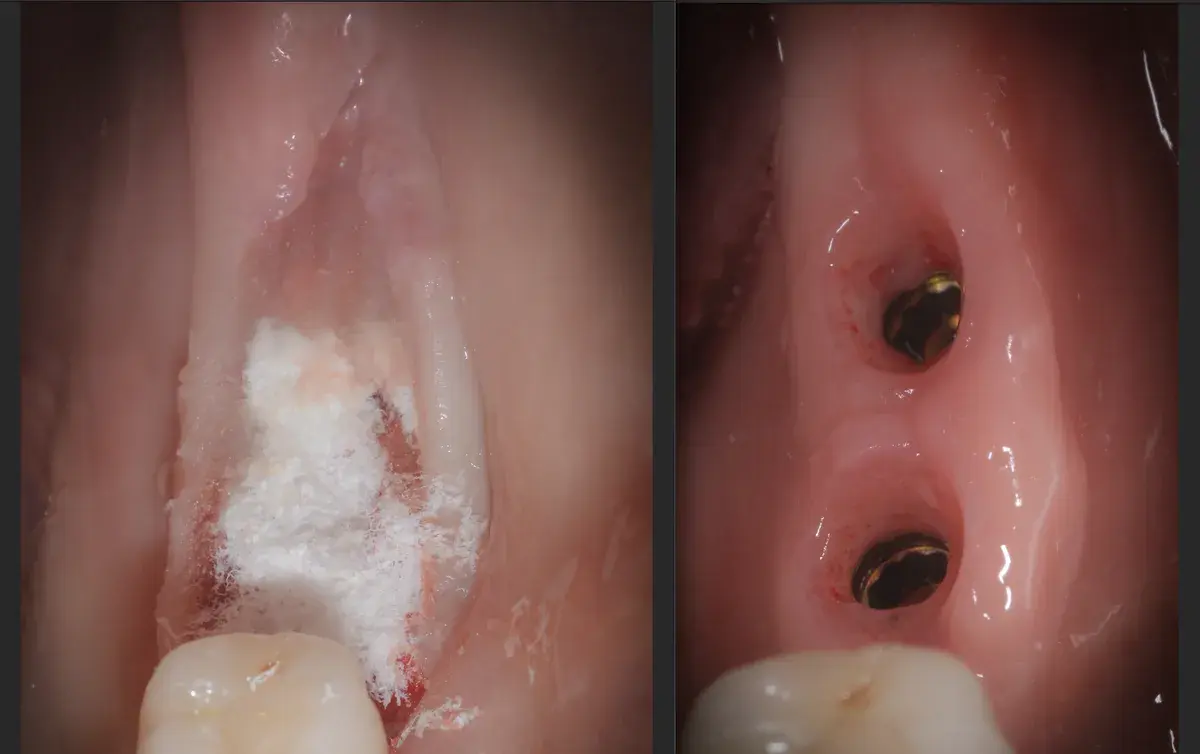

Caso clinico di sinus lift crestale immediato post-estrattivo con innesto eterologo e colla di fibrina, espansori Kalodon. Follow-up CBCT a 2 mesi.

Caso clinico di carico immediato su rialzo crestale del seno mascellare con espansori. Espansione apicale, stabilità >50 Ncm, provvisorio immediato e co...

Bonebenders: espansione osteo-mucosa naturale per impianti. 100% osso e mucosa cheratinizzata senza biomateriali. Caso clinico e risultati straordinari.

Paper 2024 su Gingival Open-Wound Technique: "innovazione" o riscoperta? Dr. Bruschi documenta guarigione per seconda intenzione nell'implantologia da...

Scopri come il tuo corpo guarisce naturalmente senza suture. La guarigione per seconda intenzione: il processo che rigenera osso e tessuti per impianti ...